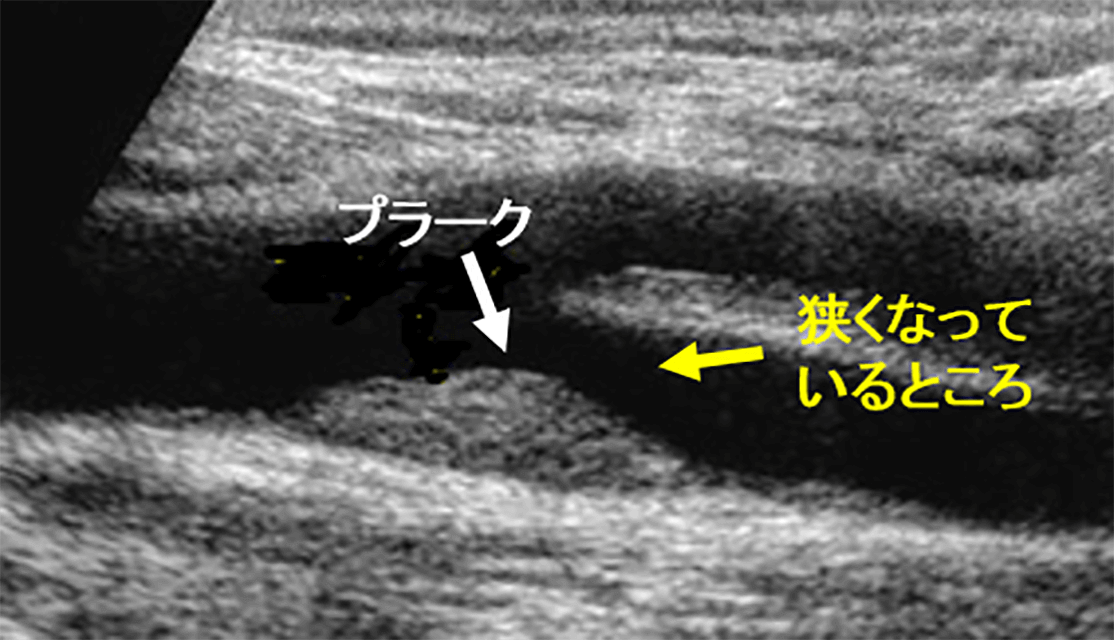

超音波(人の耳には聞こえない高い周波数の音波)を体の表面にあて、体内の臓器を画像化し、臓器の形態や血流情報をリアルタイムに観察する検査です。

頸動脈の血管壁の厚さ(IMT)、プラーク(動脈硬化に伴う血管壁の隆起病変)による血管内の狭窄や閉塞の有無、血流の状態などを観察します。

頸動脈の血管壁の厚さは、全身の動脈硬化の指標となります。